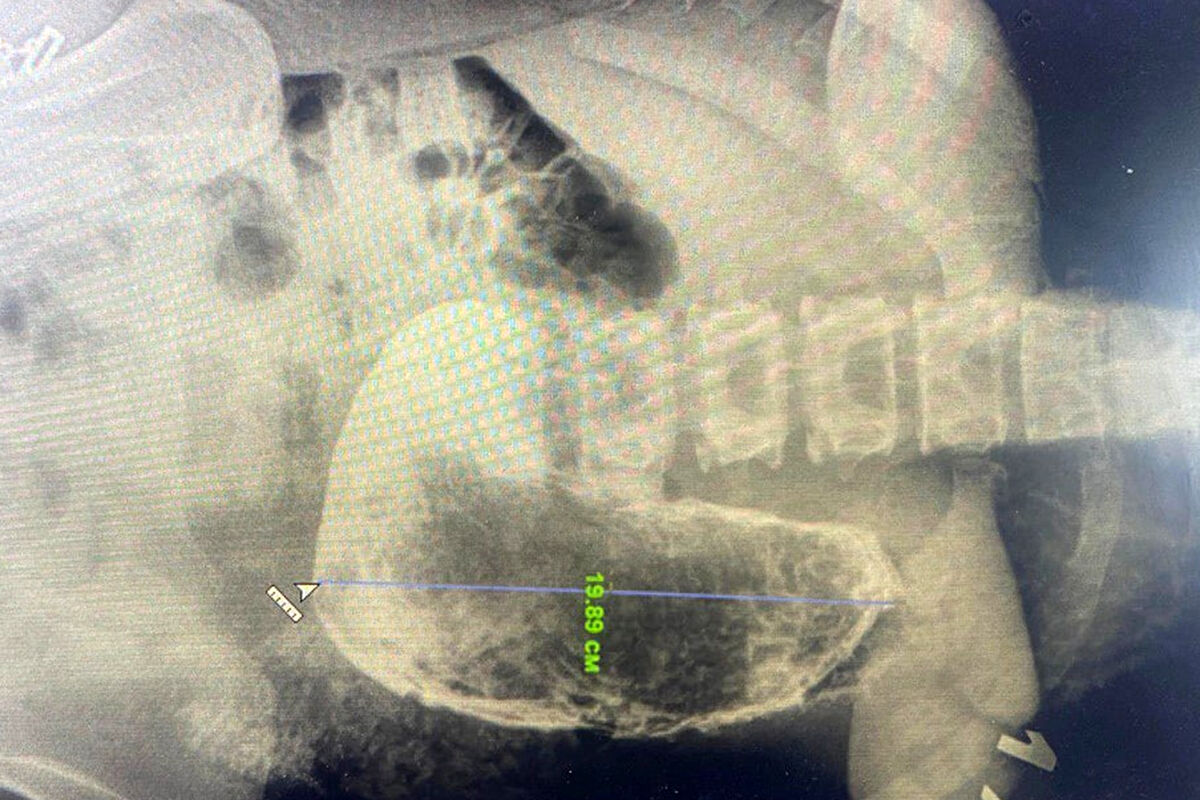

19-летняя девушка поступила в медицинское учреждение с жалобами на сильные боли в области живота, рвоту и тошноту. В ходе обследования врачи обнаружили в желудке пациентки инородное тело размером 20 см.

«Из-за больших размеров и плотной консистенции желудочного камня, мы приняли решение провести операцию, в ходе которой удалили образование через небольшой разрез. О составе безоара и причинах его возникновения более точно можно будет говорить, когда будут готовы результаты гистологического исследования», — рассказал заведующий хирургическим отделением Красногорской больницы Николай Мурашов.